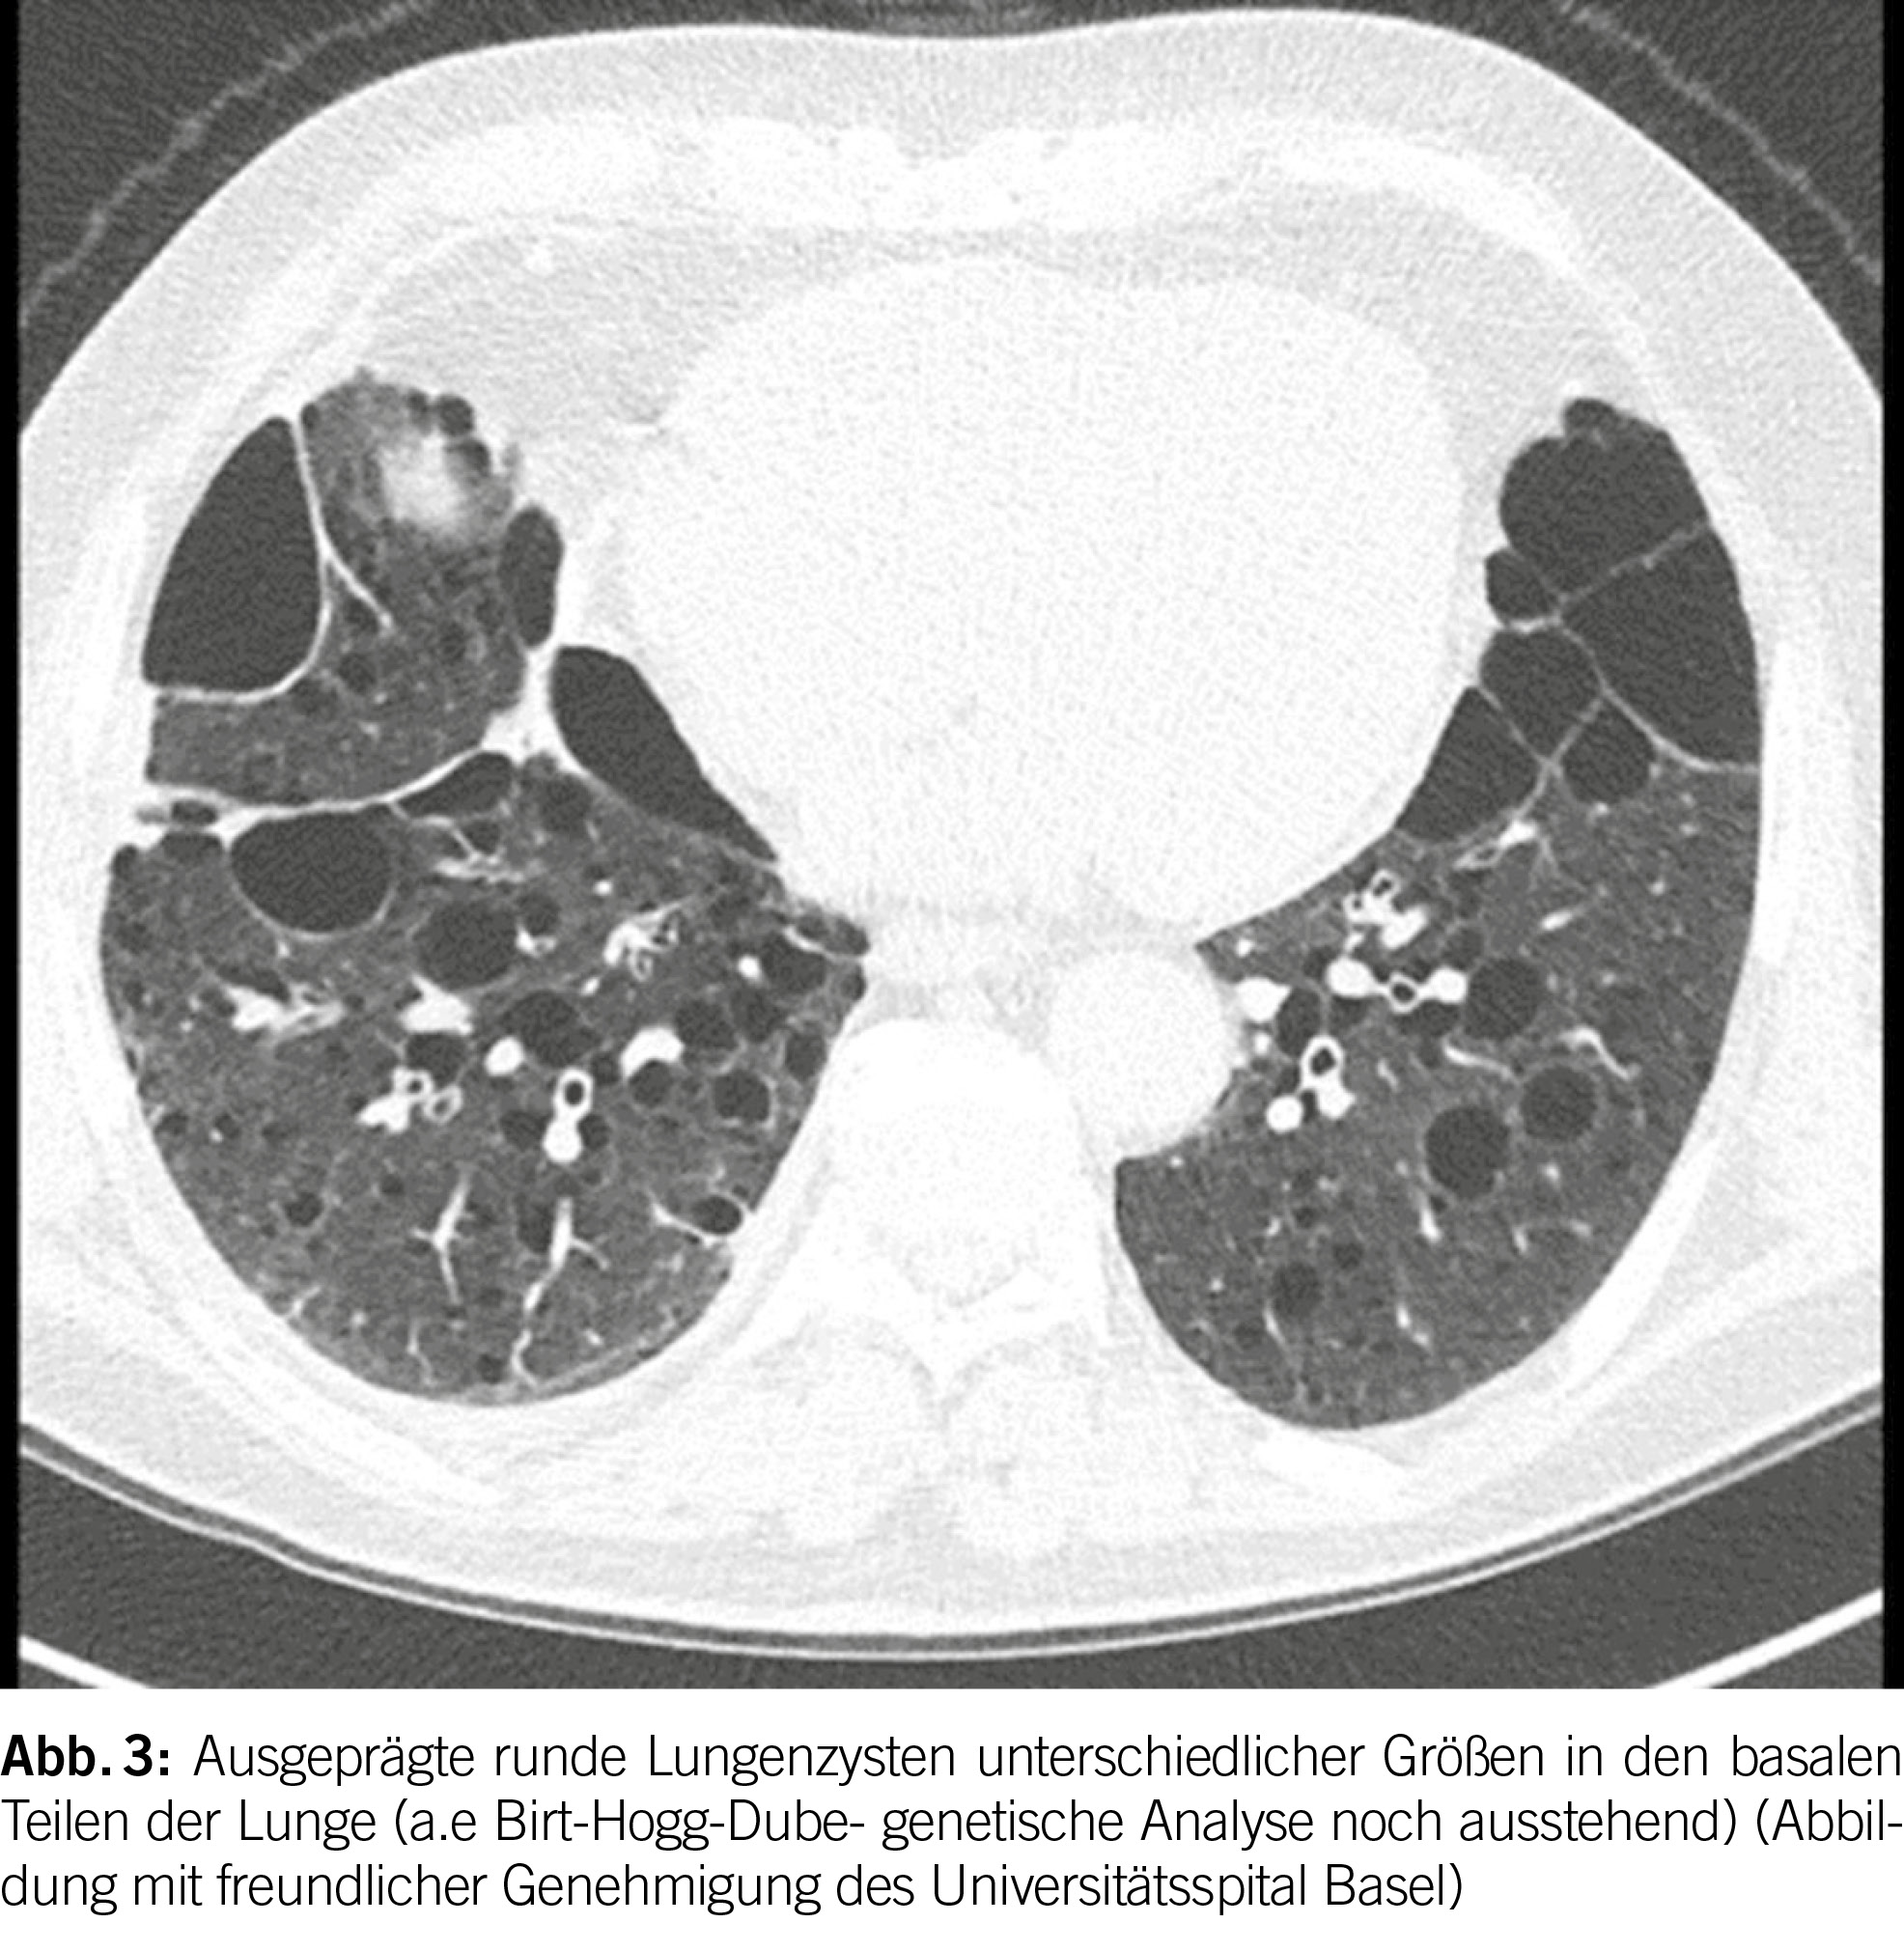

Das Birt-Hogg-Dubé Syndrom (BHD) ist eine seltene autosomal dominante Störung mit einer hohen Penetranz (geschätzt bei 90-95%) (1). Sie entsteht aufgrund von Keimbahnmutationen im Tumorsuppressorgen FLCN, das auf Chromosom 17p11.2 liegt und das Folliculin-Protein codiert. Die phänotypischen Merkmale der Krankheit umfassen eine Triade aus diffusen pulmonalen Zysten, Hautläsionen und renalen Neoplasien unterschiedlicher Histologie. Es betrifft in der Regel junge Erwachsene ohne Geschlechtspräferenz und tritt überwiegend bei Personen im Alter von 20 bis 40 Jahren auf; es kann jedoch in allen Altersgruppen auftreten. Bei BHD werden bei der Mehrheit der Patienten (ungefähr 80%) pulmonale Zysten beobachtet. Diese Zysten weisen im Vergleich zu anderen diffusen zystischen Lungenerkrankungen (DZLE) eine linsenförmige Form, größere Abmessungen und eine basale Dominanz auf (Abbildungen 2 und 3). Eine Studie zu radiologischen Merkmalen, die mit den vier Hauptursachen diffuser Lungenzysten assoziiert sind, zeigte eine deutlich höhere Inzidenz von paramediastinalen Zysten bei Personen mit BHD (2).

Die klinischen Manifestationen der Lungenbeteiligung bei BHD sind unspezifisch und werden hauptsächlich durch ein erhöhtes Risiko für die Entwicklung eines Pneumothorax charakterisiert (etwa 50-mal höher als in der Allgemeinbevölkerung) (3). So entwickeln etwa 24% der Patienten mit Lungenzysten bei BHD einen Pneumothorax mit einer sehr hohen Rezidivrate von 75% (1).